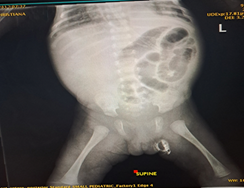

Findings at surgery include ileocecal intussusception with apex in the caecum with the involved bowel segment viable as seen in Figure 2 and an ileoileal intussusception with gangrenous ileal segment (Figure 3).

Figure 2 showing ileocecal intussusception.